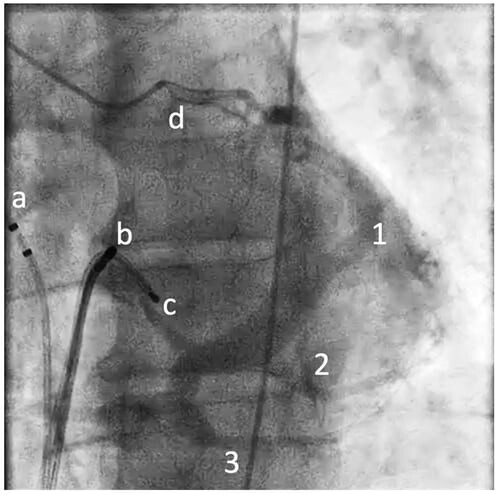

Nach femoraler, venöser Punktion erfolgte die Positionierung eines multipolaren diagnostischen Katheters im hohen rechten Vorhof (HRA-), in HIS-Position und im rechten Ventrikel (RV). Der Versuch einen mehrpoligen Koronarsinus-(CS) Katheter zu platzieren war frustran, ebenso der anschließende Versuch einer direkten Angiographie des CS (AL1, AL2, RA Angiographie mittels Pigtail), die in Anbetracht der vermuteten septalen Lage der Bahn angestrebt wurde. Über eine transradial geführte Koronarangiographie wurde die CS-Anatomie indirekt dargestellt: Es zeigt sich kein CS-Divertikel, jedoch eine Anomalie des Koronarvenensinus mit atypischer Drainage in den rechten Vorhof (Abbildung 3), sodass auf einen CS-Katheter verzichtet wird.

Abbildung3

Abbildung 3: Indirekte CS-Angiographie in LAO: prominente V. cardiaca magna (1), normal große V. cardiaca media (2), Anomalie des CS mit atypischer Drainage möglicherweise mit Konfluieren einer V. cardiaca parva (3) in den rechten Vorhof, mehrpoliger diagnostischer Katheter in HRA-Position (a), HIS-Position (b), RV (c), Führungskatheter in LCA (d)

Der Fall zeigt die Variabilität des Koronarvenensystems. Die Elektrophysiologische Diagnostik oder eine Implantation von CRT-Systemen kann dadurch zumindest erheblich erschwert werden. Neben beschriebenen CS Anomalien wie hypoplastischer oder vergrößerter CS, Fehlen des CS, persistierende linke obere Hohlvene, Koronarsinusdefekt (Kommunikation zw. CS und LA, auch „unroofed CS“ genannt)3,4 existieren weitere Anomalien, die eine Sondierung erschweren oder nicht zulassen. Die Anatomie kann über eine Koronarangiographie indirekt dargestellt werden.